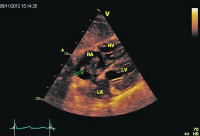

Parasternaler Längsschnitt

Abbildung 1: Parasternaler Längsschnitt: Kleiner hyperkontraktiler linker Ventrikel. Leichte Klappensklerose. Dilatation und Hypokontraktilität des rechten Ventrikels.